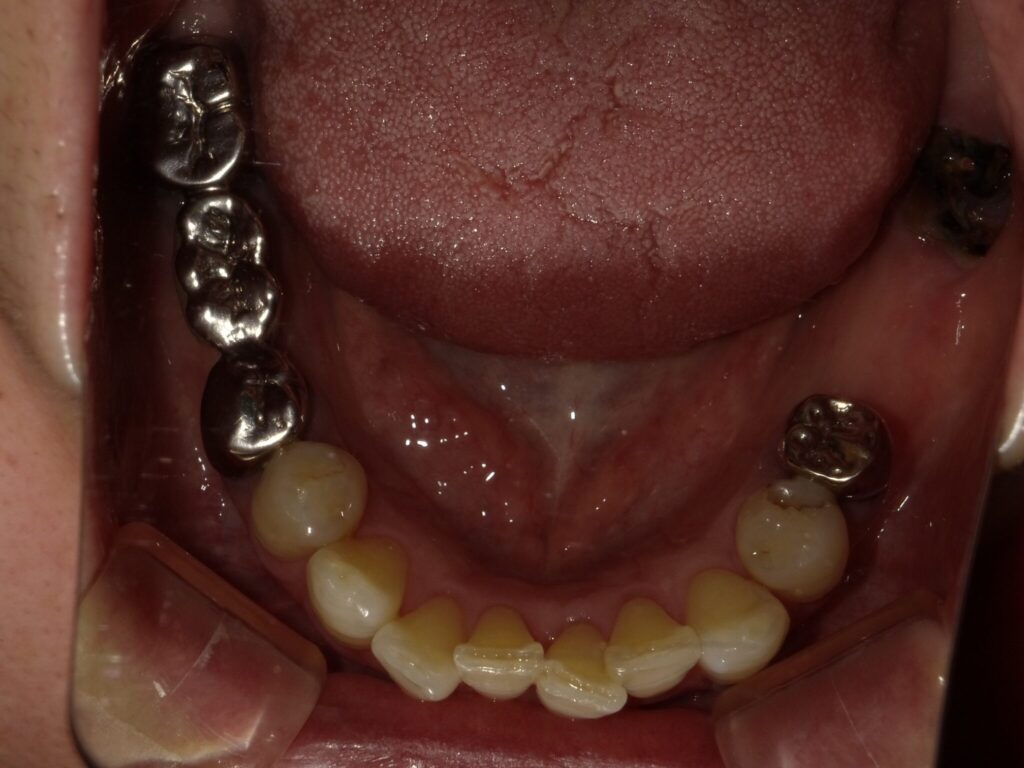

| 主訴 | 全体的に見た目を綺麗にしたい。奥歯でしっかり噛みたい。 |

| 診断名・ 主な症状 |

臼歯部欠損 |

| 治療内容 | インプラント埋入(右上4・6,左上4・6,右下6,左下6) ジルコニアBr(右上3―左上3) ジルコニア(右下5,左下5) |